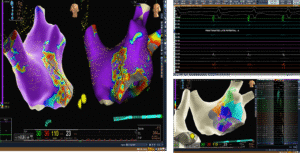

Ablation Strategy: Correlation with ILAM and Voltage Map

The ablation strategy involved correlating:

-

Isochronal Late Activation Mapping (ILAM)

-

Voltage mapping of the left atrium

The critical isthmus was identified along the anterior mitral region.

An anterior mitral line was drawn using an irrigated ablation catheter with:

-

Power: 35 W

-

Temperature: 43°C

As shown on, the linear lesion connected anatomical landmarks to interrupt the re-entry circuit permanently.

Creating a complete conduction block across this line is essential to prevent recurrence.